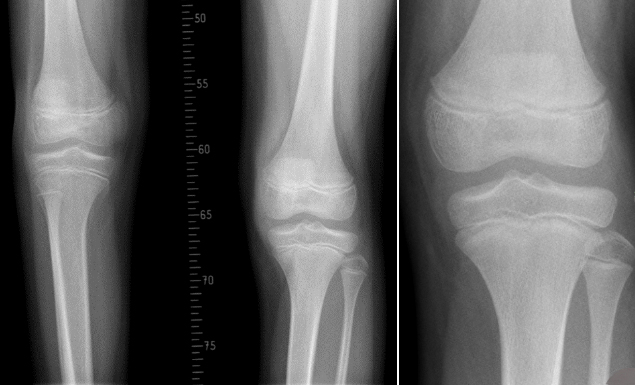

Besteht eine tatsächliche Beinlängendifferenz, ist es wichtig, mittels mehrerer Kontrollen und Messungen (dazu ist im Normalfall ein Röntgen notwendig), eine Längenabschätzung bis Wachstumsabschluß zu erstellen. Damit kann berechnet werden, wie groß und vor allem auch wo (am Ober- oder Unterschenkel) die Differenz bis zum Wachstumsende ausmachen wird. Hilfreich sind dabei auch Röntgenbilder mit aufgedrucktem Zentimeter-Maßstab (Orthoradiographie)

Bei Differenzen über 2 bis 3 Zentimetern sollten operative Therapien überlegt werden. Ist das Wachstumsende (Pubertät) noch nicht erreicht, kann mittels einer perkutanen Technik (minimale Technik über Stichinzision von ca 5 mm Länge) in Volnarkose die Wachstumsfuge des längeren Beines im Wachsen gestoppt werden. Der Patient hat danach kaum Schmerzen, muß für 3 Wochen mit Stützkrücken gehen und fällt für 6 Wochen vom Laufsport aus. Ansonsten bestehen keine Einschränkungen. Diese Operation erfolgt üblicherweise um das 11.bis 12. LJ bei Mädchen und das 13. LJ bei Knaben und erfordert eine noch offenen Wachstumsfuge. Nach Wachstumsabschluß ist diese Methode daher nicht mehr zielführend.